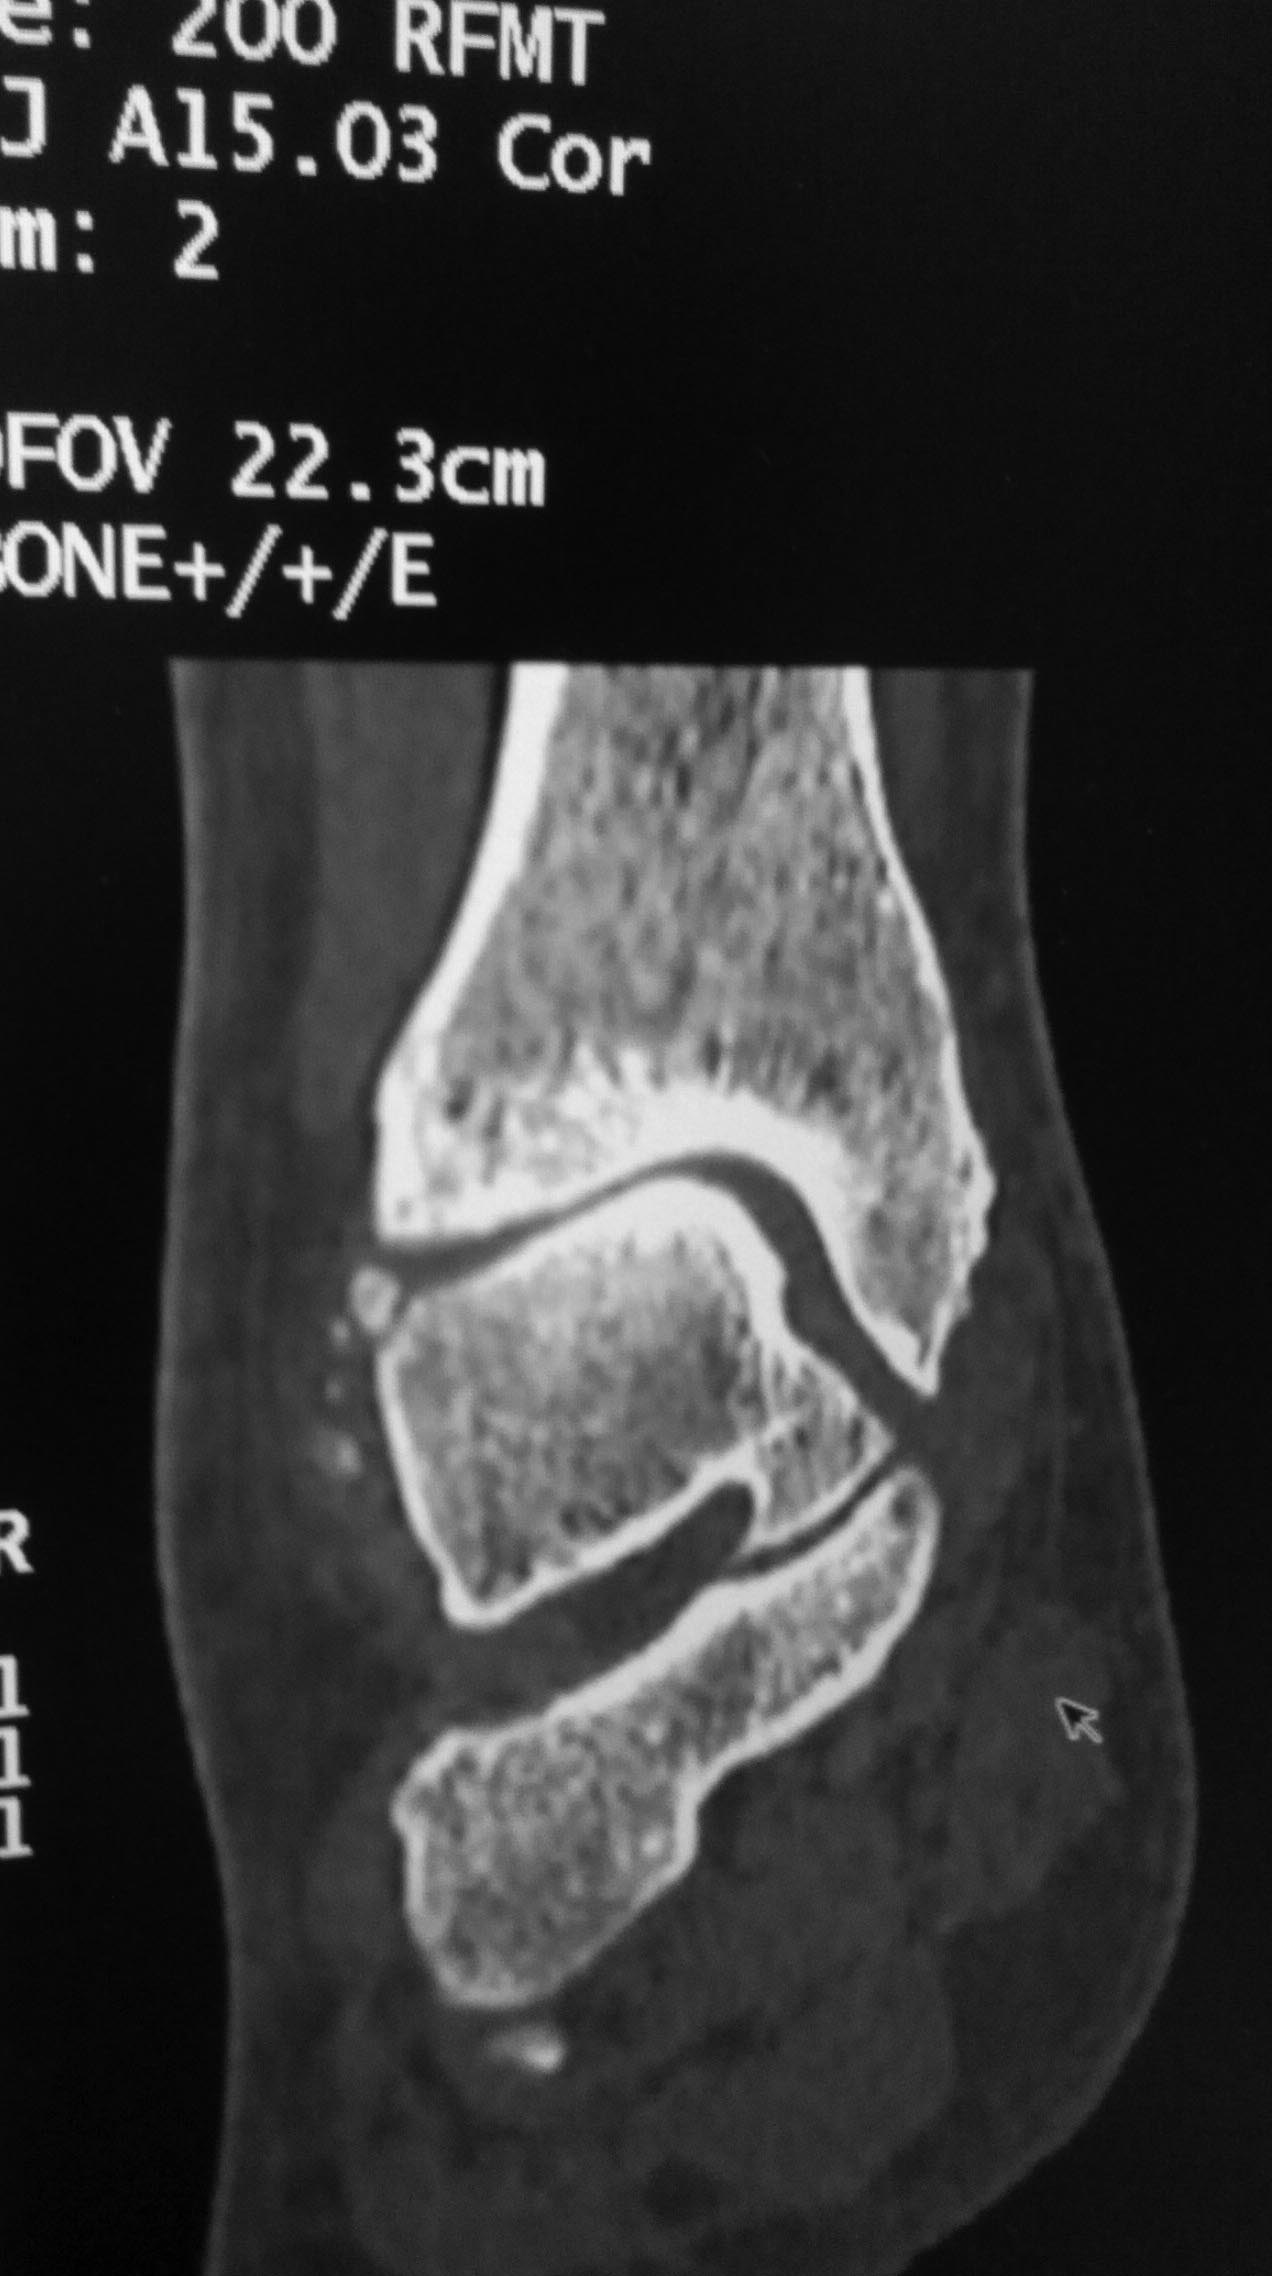

Насчет "движения в полном объеме" - хорошо бы увидеть функциональные рентгенограммы в сравнении со второй ногой. То есть снимки в профиль в крайних положениях тыльной и подошвенной флексии. Не активных, понятное дело, а пассивных, т.е. с приложением внешней силы для выведения в крайнее положение.

Интересный случай. А рентген сделан под нагрузкой? Не похоже. Обязательно нужно под нагрузкой сделать. И обещанной КТ что-то не видно. Артроз тут, конечно, есть. Хотя далеко не крайняя степень. Думать об артродезе вроде рановато. Но и какого рада корригирующая остеотомия могла бы помочь тоже по этим снимкам не скажешь.

Снимки сделаны без нагрузки. Как будет возможность, выложу Rg с нагрузкой и фото с объемом движений.

Желательно все-таки точно убедиться в наличии перелома таранной кости. Если он не сросся за 3 года, то ситуация становится еще более непонятной. Ждем снимков под нагрузкой и дополнительных срезов КТ.